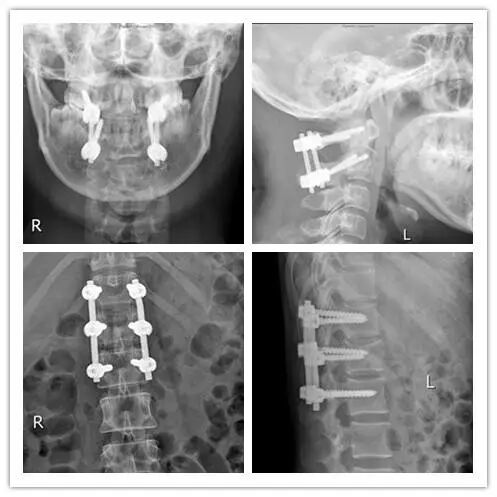

颈髓是仅次于大脑的神经中枢,决定呼吸、心跳、活动、感觉。创伤后的骨折、出血、水肿等随时可能损伤颈髓,引起瘫痪甚至死亡,手术刻不容缓。同时手术难度也是巨大的,固定高颈段的骨折堪称骨科手术的巅峰,颈椎第一、二节的椎弓根也就5毫米粗,而固定用的钢钉有3.5毫米,必须精准无误地钉进椎弓根内,往外1毫米,伤及椎动脉,往内1毫米,伤了脊髓,手术都算是失败的,甚至危及生命。

凭借丰富的临床经验和熟练的配合,经过3个多小时紧张的手术,顺利地完成骨折复位和固定。颈椎第一、二节的椎弓根也就5毫米粗,而固定用的钢钉有3.5毫米,必须精准无误地钉进椎弓根内,往外1毫米,伤及椎动脉,往内1毫米,就会伤了脊髓。

这是一场手术刀的芭蕾舞,对于我们而言,不允许任何1毫米的误差,椎弓根钉牢牢的钉在骨质中心。

腰椎爆裂性骨折经过微创复位,椎管开窗探查减压,没有对结构造成很大的影响,利于术后愈合。术中出血少,未输血。

手术很成功,周主任用术中X片机透视见骨折复位良好,内固定在位,病人可以活动手脚,才放心休息。